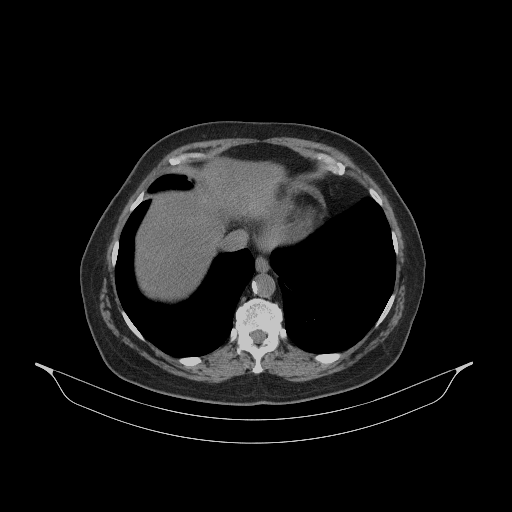

Generated VENOUS CT scan (A→B translation)

Full window (WL 1023.5, WW 4095 β†’ Low βˆ’1024, High +3071)

Lung window (WL -600, WW 1500 β†’ Low βˆ’1350, High +150)

Mediastinum window (WL 40, WW 400 β†’ Low βˆ’160, High +240)